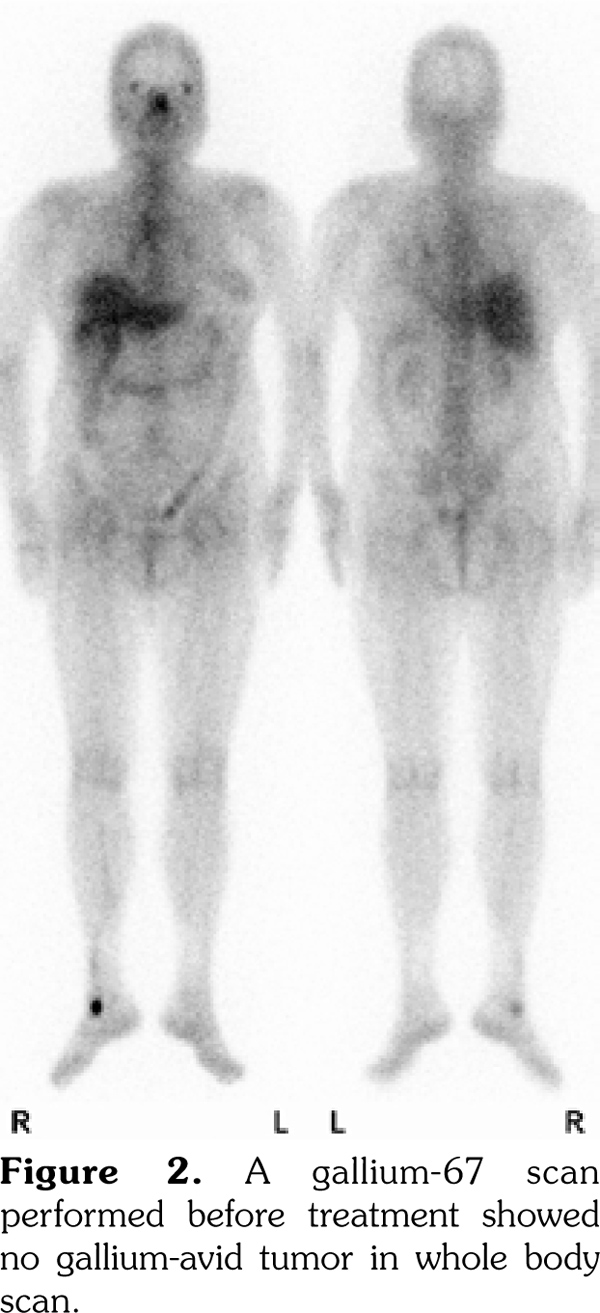

A 53-year-old female patient suffered from pain in almost her entire body, particularly the joints. Chest computed tomography revealed multiple lymphadenopathies over cervical, mediastinal, and axillary areas. A fluorine-18-deoxyglucose (FDG) positron emission tomography/computed tomography (PET/CT) revealed increased FDG uptake in many lymph nodes and the spleen. Lymphoma was suspected. However, the result of a biopsy showed no malignancy, and the gallium-67 citrate scan showed no gallium-avid tumor throughout the whole body. Adult-onset Still's disease was diagnosed and the patient responded well to steroid therapy. The follow-up PET/CT six months later showed complete remission of the FDG-avid lesions seen in the previous PET/CT. Our study suggests that FDG PET/CT combined with gallium-67 scan may be helpful in diagnosing patients with adult-onset Still’s disease. In addition, the use of FDG PET/CT alone may be useful for the evaluation of disease distribution, disease activity, and therapeutic response.

A 53-year-old female patient suffered from pain over most of her body, particularly the joints and the throat. In addition, skin rashes on the trunk without pruritus were noted. She had visited the Rheumatology, Neurology, and Orthopedic Outpatient Department several times. A chest computed tomography (CT) was performed which revealed multiple lymphadenopathies over cervical, mediastinal, and axillary areas. A positron emission tomography (PET)/CT revealed increased fluorine-18-deoxyglucose (FDG) uptake in many lymph nodes including the bilateral neck, axillae, mediastinum, bilateral pulmonary hili, abdominal paraaortic region, iliac regions, and inguinal regions as well as the bone marrow and the spleen (Figure 1). In addition, mild and diffuse increase of FDG uptake in the bone marrow was noted. Lymphoma was suspected first. After discussing with the patient, thoracoscopic mediastinal lymph node biopsy was performed. Fifteen lymph nodes were taken and the results showed histiocytic infiltration in sinusoid area and anthracotic pigment deposition. Reactive lymphoid follicle hyperplasia and focal fibrocalcified nodule formation were also noted. No tumor cell was seen. Gallium-67 (Ga-67) scan was conducted and no gallium-avid tumor was seen throughout the whole body (Figure 2). The laboratory data were negative for antinuclear antibodies, rheumatoid factor- immunoglobulin M, and extractable nuclear antibody, while alanine aminotransferase was high. The final diagnosis was AOSD. In our case, there were no symptoms or signs of either high fever or debilitating joint although the FDG PET showed multiple FDG-avid lesions in the whole body scan. According to the experience of our rheumatologists, methylprednisolone (Metisone) 4 mg/day and non-steroidal anti-inflammatory drugs were prescribed initially and the response to treatment was good. Six months later, the follow- up PET/CT showed complete remission of the FDG-avid lesions seen in the previous PET/CT (Figure 1) and the patient’s symptoms relieved. A written informed consent was obtained from the patient.

In this study, we present the FDG PET/CT and Ga-67 scan findings of a patient who met the Yamaguchi classification criteria for AOSD. The FDG PET/CT scan was not helpful in diagnosing AOSD in this case since lymphoma could not be ruled out. However, the FDG PET/CT scan results were useful for evaluating the distribution and severity of the disease. A negative Ga-67 scan could be beneficial as it would exclude lymphoma. After the diagnosis of AOSD was established, the patient received nonsteroidal anti-inflammatory drugs and glucocorticoids with a good response. Disease activity and therapeutic response were monitored by FDG PET/CT and the findings of a scan performed six months after treatment were negative.(13)